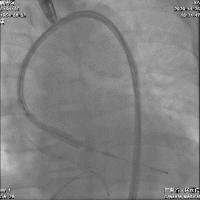

术中建立双侧股动脉入路,以右股动脉为主,送入导丝顺利跨瓣进入左室,先行球囊预扩张,处理主动脉瓣环钙化;后续沿已建立的导丝路径,送入Edwards Sapien 3球囊扩张式主动脉瓣膜置换系统,在推送的过程中,一边调弯一边缓慢推送,保证安全过弓并成功完成跨瓣。